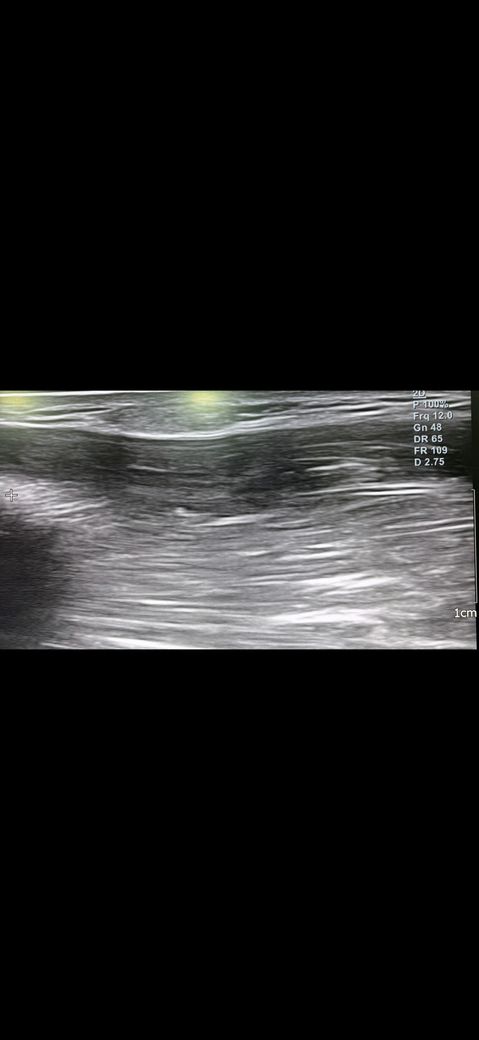

예전에 병원에서 팔에 동글동글하게 두 군데 정도 뭐가 만져지길래 초음파 사진을 찍고왔습니다.

해당 병원에서는 지방종같다고 하셨는데 생긴지 3년은 지난 것 같은데 계속 신경쓰이고 걱정이 되는데 사진의 종양이 지방종이 맞을까요?

• 1번 째 사진

초음파의 경우 정확한 진단보다는 양성 내지 악성 양상을 보는 검사 중 하나라고 생각해 주시면 좋고, 보통은 지방종의 경우 균질하고 경계가 명확한 모양을 띠고 있어, 질문자님의 사진상으로 볼 때에는 지방종일 가능성이 있겠습니다. 휴미라의 부작용으로 지방종을 유추하기에는 아직까지 연구된 부분이 없어서 부작용으로 보기에는 어려울 것으로 사료됩니다.